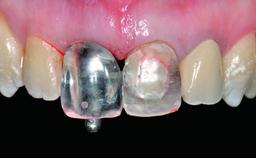

A 23-year-old female, healthy and non-smoking patient had had tooth 11 temporarily restored following a trauma in adolescence. As the patient’s growth had since come to an end and the crown had fractured, she requested an implant-supported restoration of tooth 11. Moreover, the contralateral tooth 21 presented an old composite restoration at the mesial incisal edge. The periodontal tissues were healthy with periodontal probing depth values below 3 mm, but some inflammation was observed around the semi-submerged root of tooth 11.